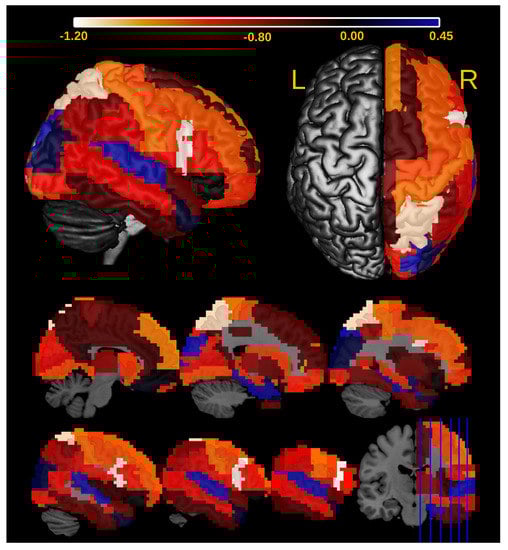

3.2. Application